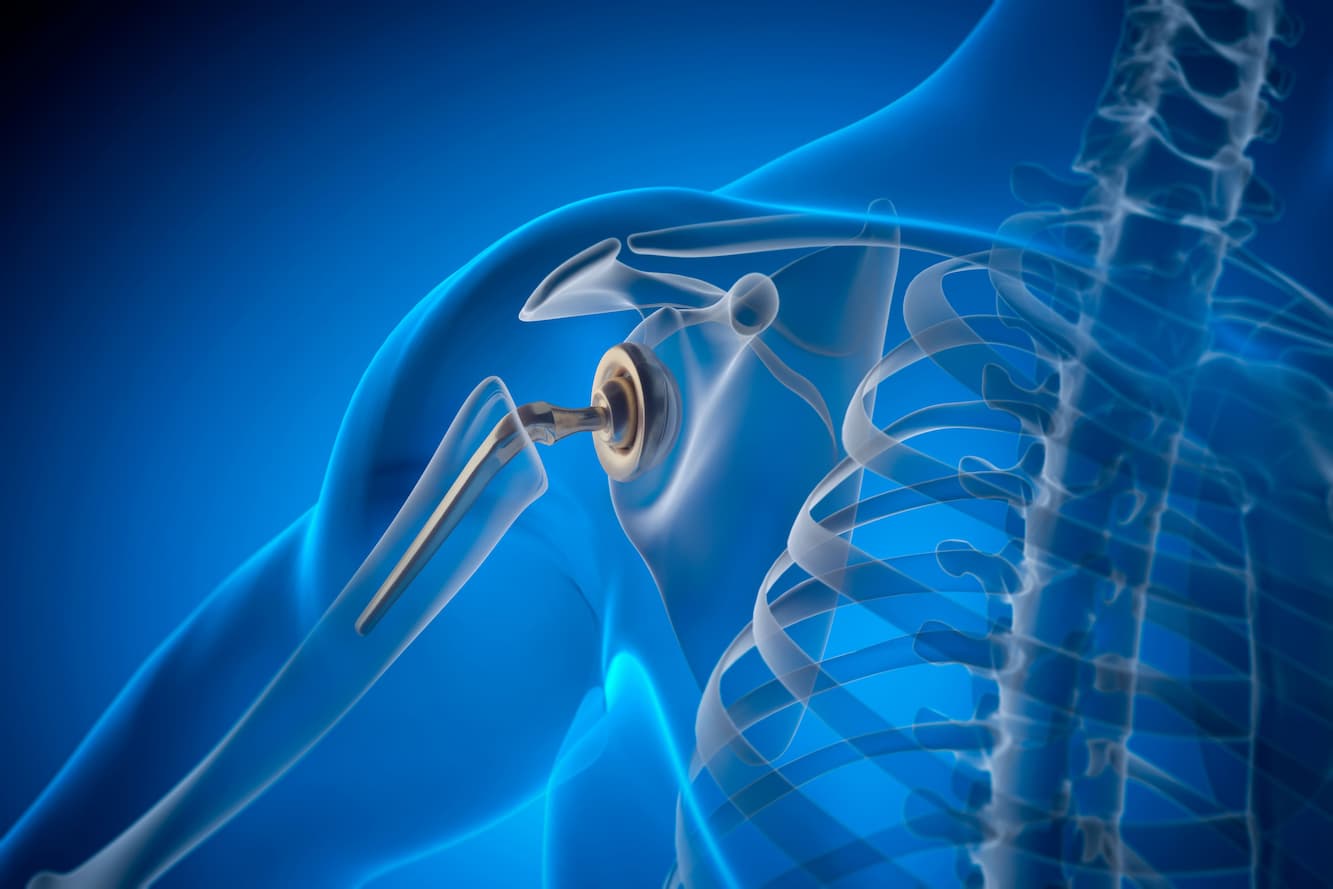

MedVoyage collaborates with highly skilled surgeons at partner hospitals who utilize the latest techniques and possess a profound understanding of the musculoskeletal system. Our goal is to help you regain your freedom of movement, joint by joint.

MedVoyage collaborates with highly skilled surgeons at partner hospitals who utilize the latest techniques and possess a profound understanding of the musculoskeletal system. Our goal is to help you regain your freedom of movement, joint by joint.